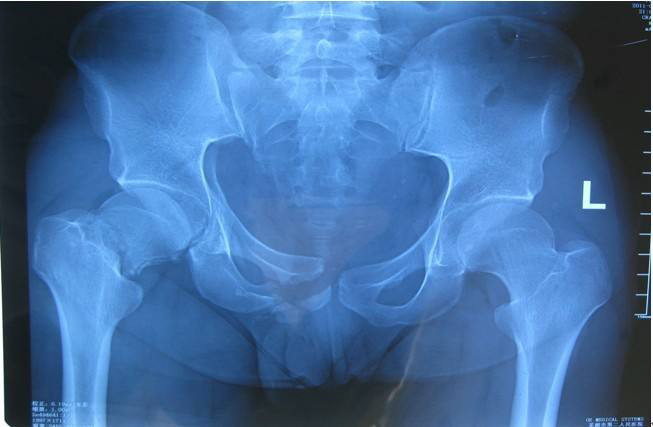

骨盆环是一个骨性环,由后方正中的骶尾骨与两侧各一块的髋骨组成,髋骨由髂骨、耻骨和坐骨三部分组成,三骨交汇处形成髋关节的髋臼。骨盆环的后方有骶髂关节,前方有耻骨联合,相互之间有许多坚强的韧带,构成一个坚固的骨环。 >>>骨盆骨折和髋臼骨折的区别?点击咨询

髋臼骨折早期主要表现为髋关节局部疼痛及活动受限,如并发股骨头脱位则表现为相应的下肢畸形与弹性固定。当发生髋关节中心性脱位时,其疼痛及功能障碍程度均不如髋关节前、后脱位,体征也不明显,脱位严重者可表现为患肢缩短。髋臼骨折时可能并发有盆腔内大出血、尿道或神经损伤,以及骨盆环的断裂和同侧下肢骨折。>>>髋臼骨折该如何治疗?直接咨询